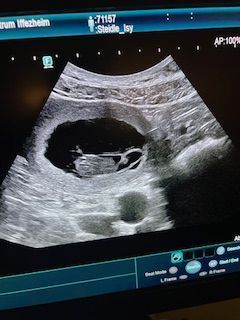

Herzlichen Glückwunsch ISY wird Mama

Es hat geklappt ! Wir erwarten Welpen ! Geburtstermin ist Mitte August ...

Wurfplanung 2025 L - Wurf - Abgabe der Welpen im September